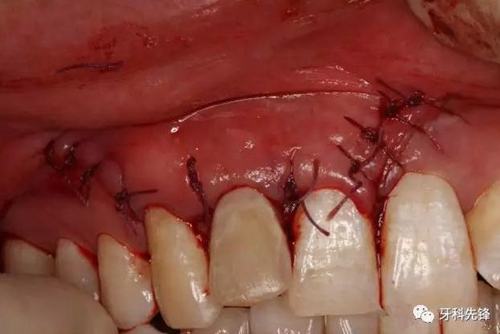

圖19縫合。